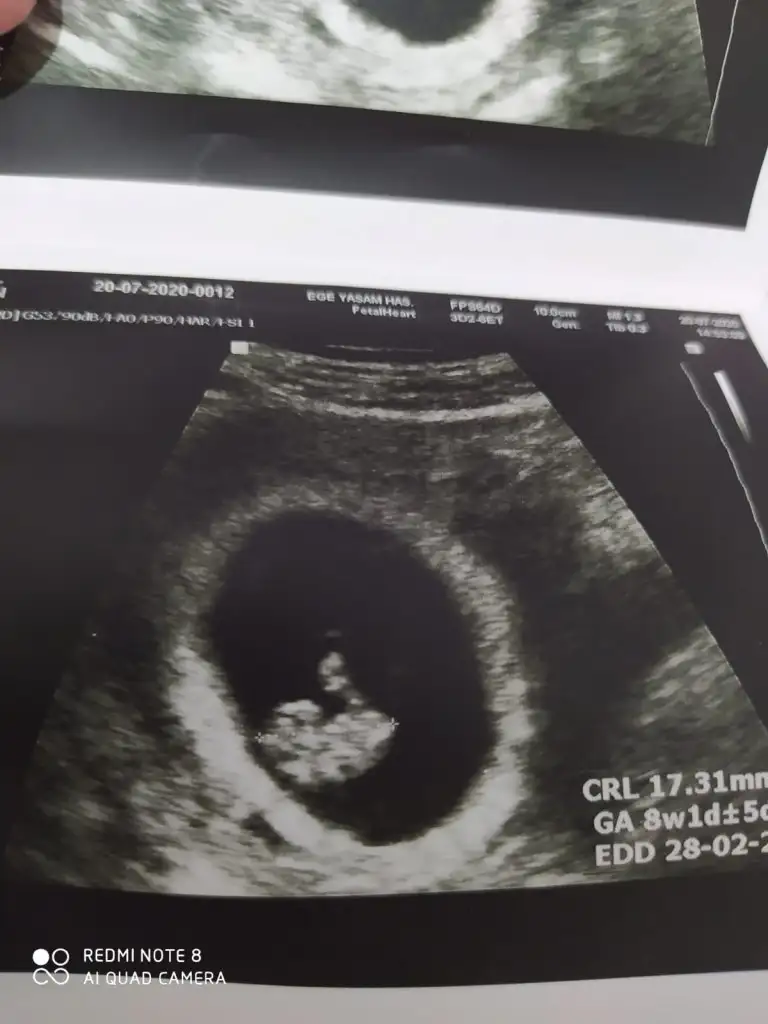

Buna göre kız tabi en iyi 11 12 13 haftalarCanım buda ablamın ultrasonu 8 haftalık tahminin nedirr